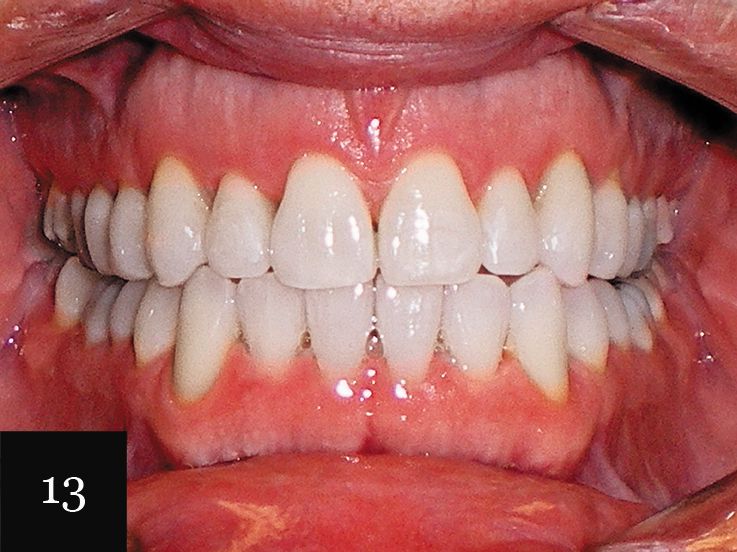

This treatment was performed on a male patient in his early 40s (Fig. 9). The patient had an omega-shaped upper arch, as seen in Fig. 10.

An impression was taken that successfully captured the complex crowding and narrow omega arch (Fig. 11), and the patient was treated with 28 aligners over 14 months. This case also illustrates use of the clear aligners as whitening trays, with the final result showing a smile that is not only straight, but also much brighter (Figs. 12-14).